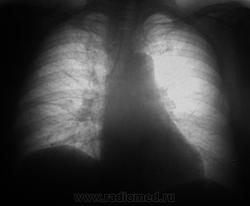

Через полтора года...

Мезотелиома!?

Пациент полтора года выращивал это ходил? По первым ФЛГ норму поставили?

Выросло,однако.

Нет. Просто гражданин исчез.

Вот так оно и бывает.Потом и разбираемся,кто виноват и что делать.